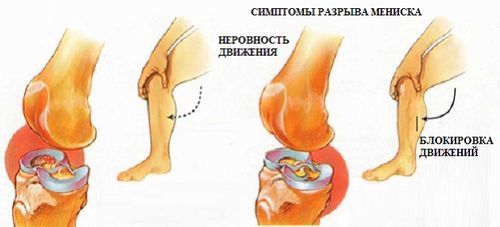

Характерні симптоми проблеми

Ось основні симптоми розриву меніска колінного суглоба:

- Защемлення меніска. Трапляється, у 40% населення. При защемленні задирається порушена частина і блокується суглоб. Тут потрібно вправити суглоб, але якщо це не допоможе, то тоді буде потрібна операція.